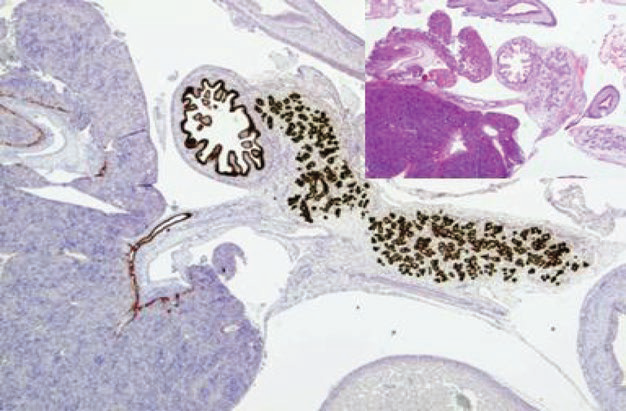

图1. 本例为12周胚胎组织,免疫组化PDX-1在胰腺导管、十二指肠黏膜、胆管黏膜都有表达。